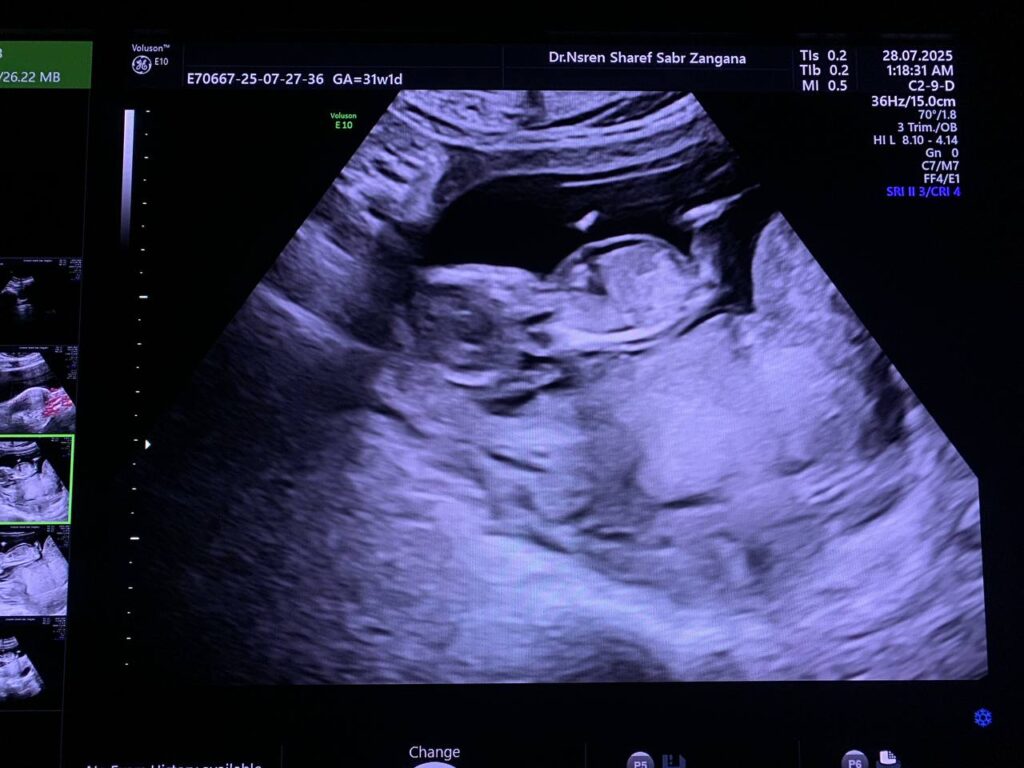

Diffuse edema with Increase nuchal translucency 6.7mm , hypoplastic nasal bone , picture mostly of hydrops fetalis with chromosomal anomaly , please for further study

CRL= 12w+6d